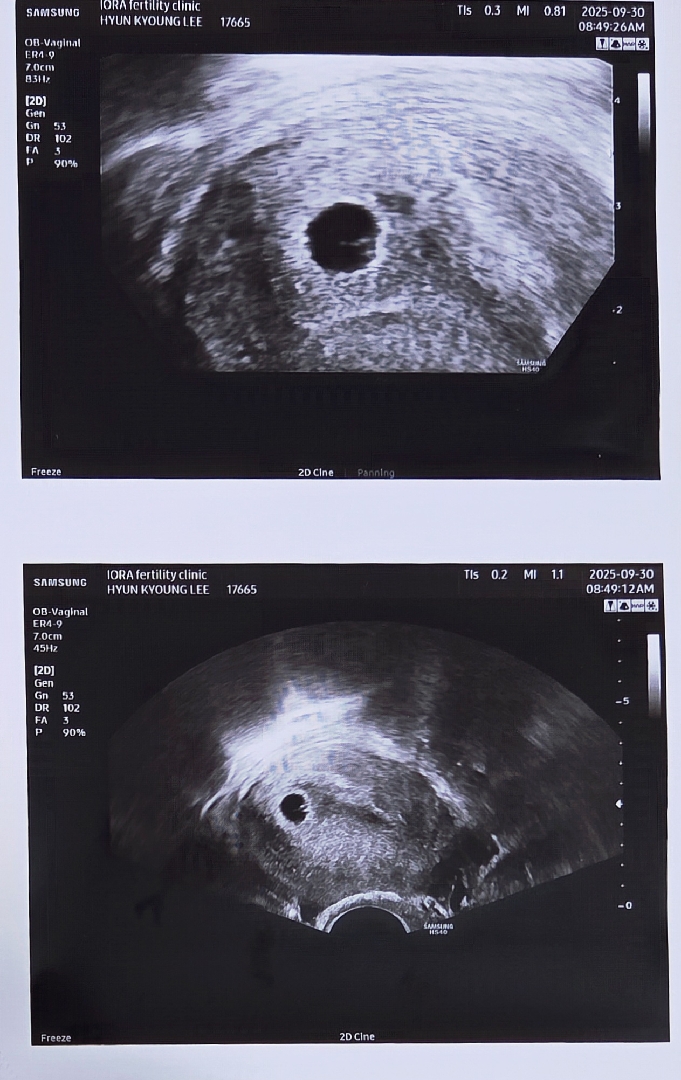

안녕하세요^^ 저랑 비슷하시네용 저 오늘 5주 5일차에요 지난주말 아기집 보고왔고 아직 난황은 안보이네요 전

5주3일차 임산부^^

4주6일차에 첫초음파로 아기집, 난황 확인했어요~ 저랑 날짜 같은 동기분 계실까요? [질문] 4주6일차 기준 수치 15199, 저처럼 높게 나오신분 계신가요? 아무생각없이 1500인줄 알았는데 다시보니 만오천이네요-_-

저랑 주수 똑같으시네용~! 저는 딱 5주차에 가서 아기집만 보고왔는데 2주뒤 예약 잡고왔는데 설레요~~~